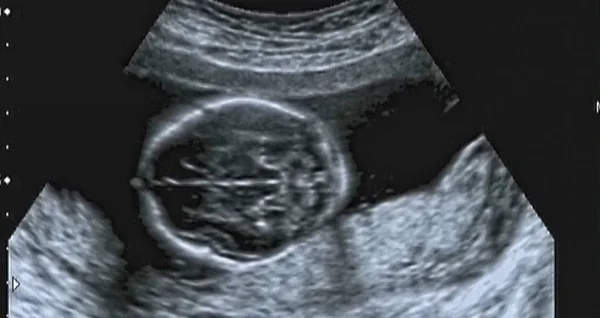

What Does A Baby Girl Look Like On Ultrasound

Beza Scan Baby 2d 3d 4d 5d Dan Hd Athirahassin

Scan Bayi 2d 3d 4d Yang Mana Lebih Baik Untuk Ibu Hamil

Ini Antara Sebab Kenapa Detail Scan Untuk Bayi Lebih Penting Dari Scan 3d4d5d